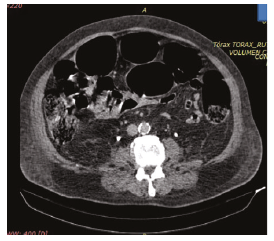

Both patients presented with large abdominal distention, bloating, and constipation. One patient developed a confusional state with hypoactive delirium. Both presented with gastric residuals. Intra-abdominal pressure (IAP) results showed hypertensive values in 1 patient and abdominal compartment syndrome in the other patient. Both required vasopressors to achieve an abdominal perfusion pressure of >60 mm Hg. Laboratory investigations showed hyperleukocytosis, elevated C-reactive protein, and kidney injury (Kidney Disease Improving Global Outcomes [KDIGO] score of 1). Abdominal radiographies showed large distention of the colon. Abdomen tomographies showed dilation of the colon, but there was no evidence of any obstruction or edema of the wall of the colon (Figure 1). The diameter of the cecum was 11 cm in 1 patient and 9 cm in the other (Figure 2). Rectal examinations did not reveal any matter inside. Intravenous neostigmine treatment was started at a dose of 2.5 mg, with both patients requiring continuous infusion at 0.3 mg/hour, which was maintained for an average of 16 hours, achieving reinstatement of the intestinal transit.

Figure 2. Abdominal Computed Tomography Scan Showing the Cecum Distended and With Fecal Matter